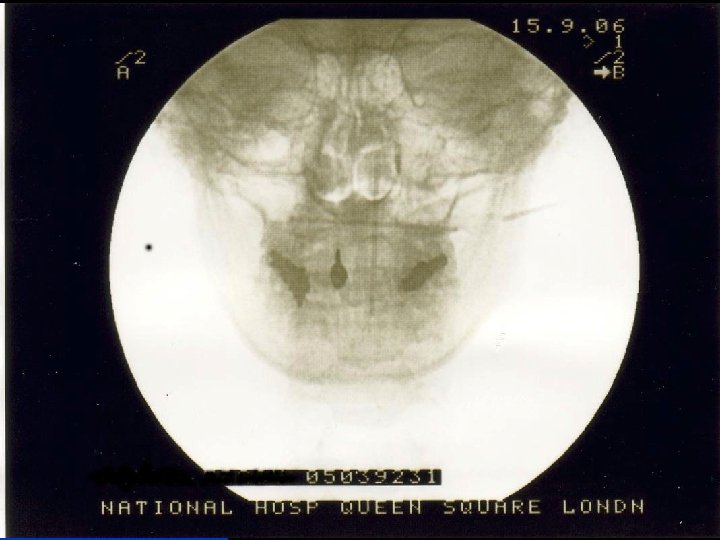

Stages of the operation n Insertion of electrodes « LA n + Sedation Test stimulation of electrodes « Awake n Insertion of battery and tunnelling of leads « Asleep n n (GA with LMA) Alternatively GA throughout if difficult airway or reflux USA: 2 stage procedure

Skin marking n n n Awake, sitting upright on stool Midline Intermastoid line Spinous process of C 1 3 cm from midline Chosen position of battery

Positioning n n Lateral position Access to all operative areas Strict aseptic technique to establish field Anaesthetist access to patient for communication and airway

Test stimulation n n Radiating occipital paraesthesiae bilaterally 300 microseconds pulse width 60 -80 Hz At low amplitude – typically 1 -2 V If no paraesthesiae or if amplitude >4 V then reposition electrode